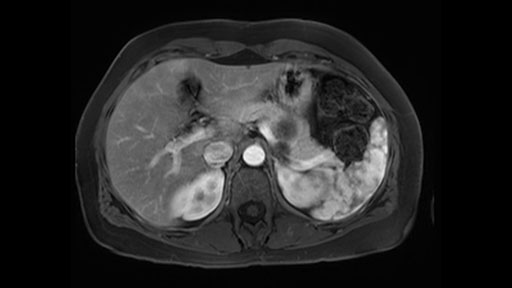

The preoperative MR is very very important; any scan for that matter. Whether it is a pancreatic protocol CT scan or the MR as presented, the diagnostic imaging plays a very big role. And with this we see that it’s a very well-defined cystic focus in the body of the pancreas. Although there are septal enhancements, very well demarcated, but there is no vascular involvement. However, the mass appears to be in contact with the splenic vessel, and the mass is also a little bit in touch with the left adrenal and also the loop of bowel. So looking at this, basing on the features, I think it’s probably a mucinous cystic lesion, it could possibly be a pseudocyst. But basing on the history, it appears like there is no history that would point out to a pseudocyst. And not an IPMN as well; I don’t see any side branches from the MRCP and the MR scan and although there is no axial T2 images available, and I truly find it easier to identify the septations on T2, and the hepatic cyst that is visible on this scan makes it hard to differentiate it from a simple or complex cyst which may be considered in a mucinous neoplasm with cystic or mucinous metastasis. Basically the contrast would help us in identifying the enhancing mural nodules or septations in the cysts. The MRCP is definitely helpful to identify if there is any side branch, if we are considering any IPMN.

So basing on this, it probably appears like this is a benign disease. We just need to make sure that we avoid the vascular structure of the splenic vessels. We try our best, meticulously, to preserve the splenic vessels, such to preserve the spleen and also to try to isolate it from the bowel loops that appears to be in contact and also spare the adrenal.